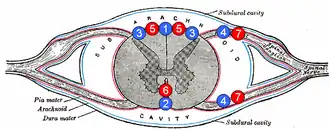

1: Posterior spinal vein 2: Anterior spinal vein 3: Posterolateral spinal vein 4: Radicular (or segmental medullary) vein 5: Posterior spinal arteries 6: Anterior spinal artery 7: Radicular (or segmental medullary) artery | |